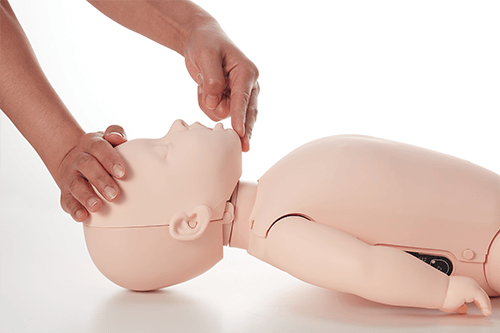

- The Brayden Baby has a realistically large occiput so the Baby lies with its head in a realistic position (in flexion).

- The head needs to be moved to open the airway in to a neutral position.

- A realistic ‘Jaw Thrust/Lift’ maneuver is possible to practice opening the infant airway as required.

- Correct positioning of the head into the neutral position to open the airway.

- Realistic occlusion of the airway for an infant when the head is hyperextended.